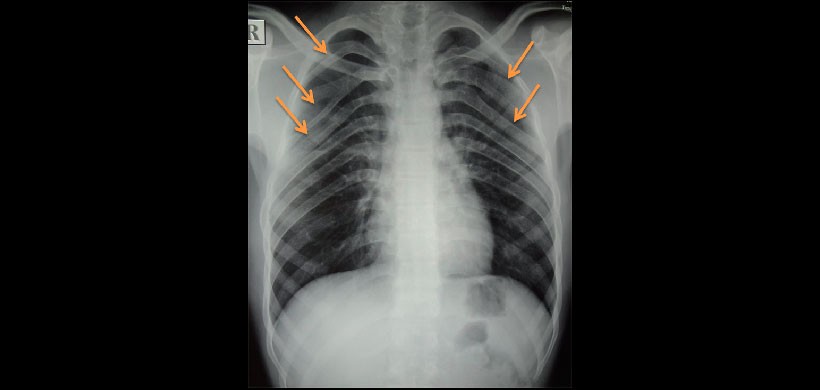

Fig 4. Radiografía de tórax, muestra la presencia de costillas bífidas.